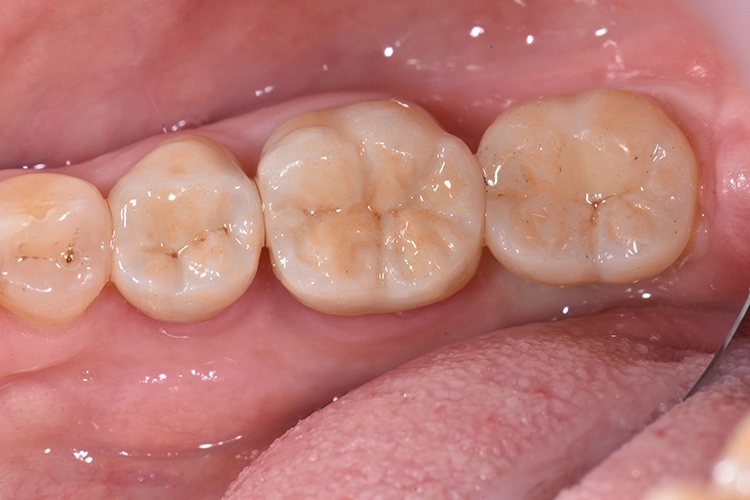

Bilder: Dr. Lampson / HannkerDie Kronen für die Zähne 45 und 46 wurden mit einem selbstadhäsiven Befestigungs-Composite (G-CEM LinkAce; GC*) auf den Pfeilerzähnen angebracht, die Krone für Zahn 47 auf das Implantat geschraubt (35 Ncm) und der Zugang im unteren Bereich mit Teflon, im oberen mit Composite gefüllt (Abb. 19). Nach Überprüfung der Okklusion wurde der Patientin das Endergebnis präsentiert.

Die CAD/CAM-Restaurationen aus Lithium-Disilikat fügten sich nahtlos in die natürliche Zahnreihe ein und wiesen perfekte, passgenaue Ränder auf. Die Patientin war mit dem natürlichen Behandlungsergebnis sehr zufrieden. Auch bei der Kontrolluntersuchung nach 2 Jahren, berichtete die Patientin nicht Negatives und befand die Kronen in Bezug auf Ästhetik und Funktion weiterhin als gelungen.